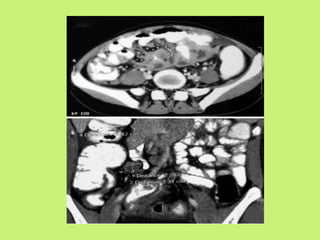

CT scan

• Abdominal CT is better than USG.

• Contrast enhanced CT is preferred.

• Most common CT finding is concentric mural

thickening of ileocecal region, with or without

proximal intestinal dilatation.

• It also shows abdominal lymphadenopathy

involving predominantly mesentaric, para-

aortic, peri-portal.